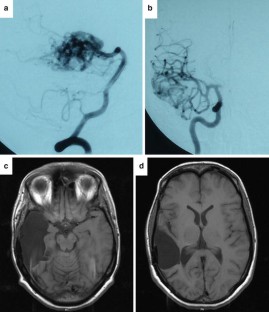

Attention deficit hyperactivity disorder (ADHD) is defined by inattentiveness, impulsivity, and/or hyperactivity and mandatorily requires an onset in childhood. Structural or functional anatomical abnormalities have mostly been found in the prefrontal cortex, the corpus callosum, the striatum, and the cerebellum. We here present the case of an adult woman who developed severe symptoms analogous to ADHD after right temporal lobectomy. Surgery had been necessary because of a large temporobasal arterio-venous malformation (AVM). The patient’s childhood and personal history before surgery had been without any indication of ADHD or any other mental disorder. Because of her distinct and impairing symptoms of ADHD, we initiated off-label methylphenidate treatment, achieving strong reduction in the symptoms. This proves further similarity of her symptomatic disorder to ADHD and supports a role of the right temporal lobe in ADHD.

Fig. 1